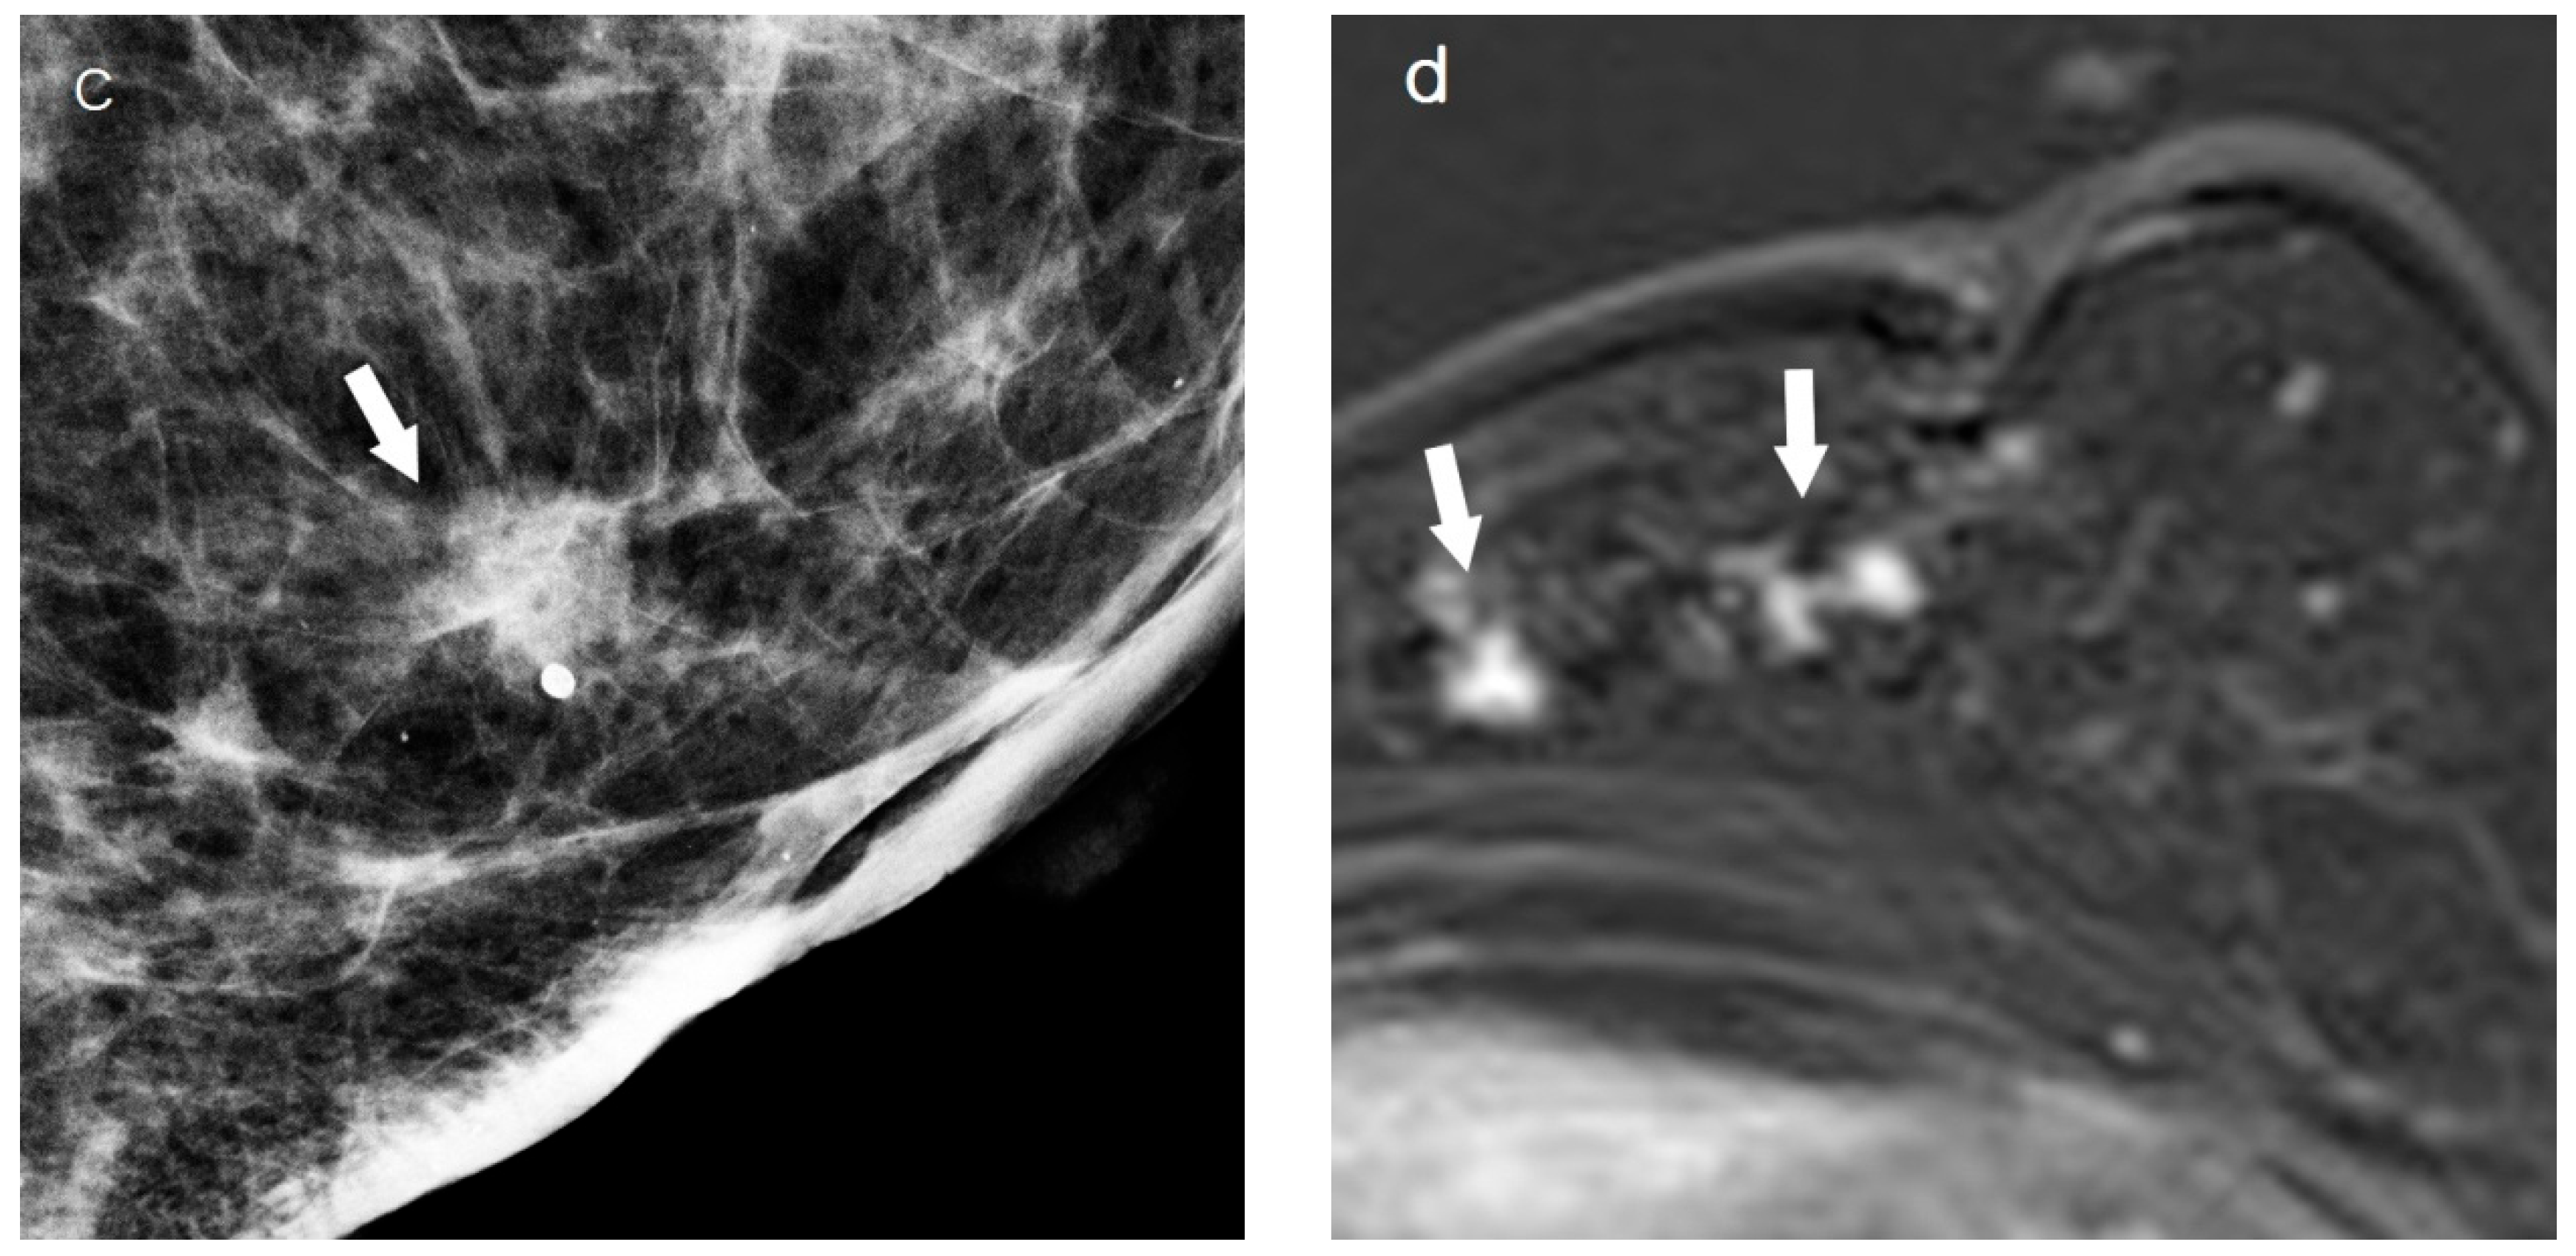

2.3. Assessment of Breast Cancer on Chest CT

2.4. Imaging Analysis

| Chest CT | ||||

| Background position | <0.001 | |||

| Fatty portion | 44 (49.4) | 5 (16.1) | 39 (67.2) | |

| Glandular portion | 45 (50.6) | 26 (83.9) | 19 (32.8) | |